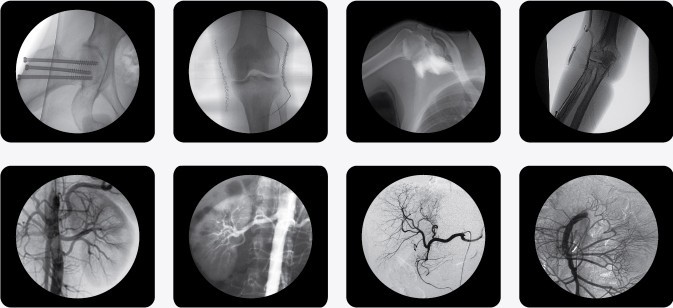

廣泛應(yīng)用于 介入科、骨科、外科、矯形外科、泌尿外科、脊柱外科、腹部外科、疼痛科、心臟科、消化科、婦科及手術(shù)室等。

三、C型臂X光機(jī)PLX7000B數(shù)字高清影像,支持您做出精確診斷

·全數(shù)字化百萬像素影像采集系統(tǒng),優(yōu)化設(shè)計(jì)和配置,為您提供高分辨率、高灰階圖像,支持您做出精確診斷。